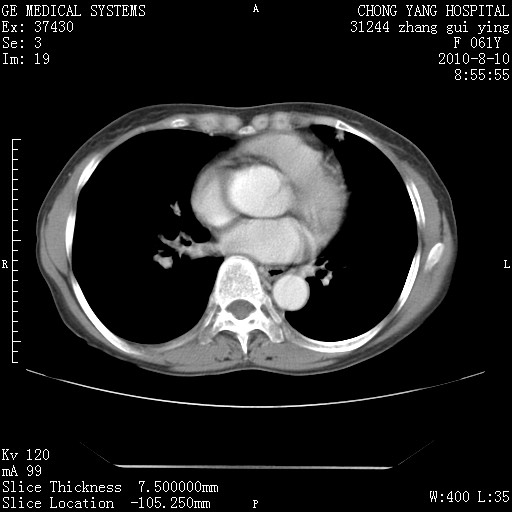

标题: CT28314:F61Y胸部增强,发热咳嗽一周入院,后面的为一周前平 [打印本页]

标题: CT28314:F61Y胸部增强,发热咳嗽一周入院,后面的为一周前平

1、支持考虑右侧中央型肺癌伴右肺中叶节段性不张及下叶支气管黏液痰栓    2、左肺上叶舌段感染。

支持3楼意见,还要考虑:纵隔及肺门淋巴结转移、右侧少量胸腔积液。

确切的说:1:右肺下叶中心型肺癌侵及中叶支气管并中叶不张,纵膈淋巴结转移。2:左肺舌叶炎症。3:右侧胸腔少量积液

块影平扫32hu,动静脉期62-70hu.